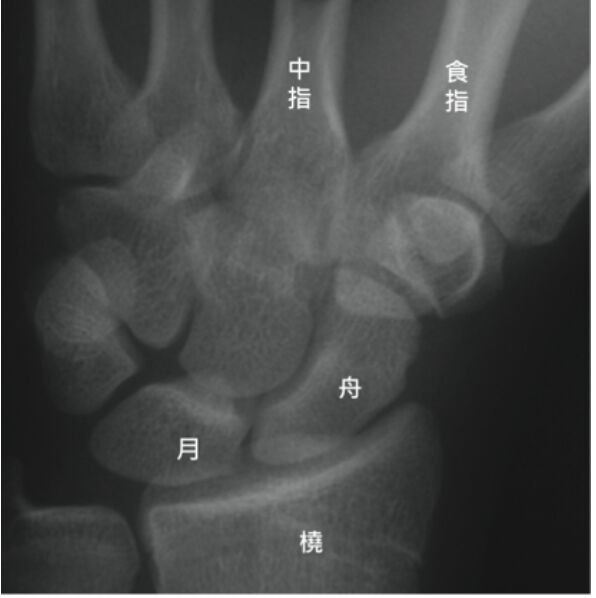

52.下列何者是腕骨近端列的中心,且是腕骨中最不穩定的骨頭?

(A)舟狀骨(scaphoid)

(B)月狀骨(lunate)

- 舟狀骨是構成手腕“腕骨”的8塊小骨頭之一,它連接了近端(靠近前臂)和遠端(靠近手指)的腕骨。

- 處於這個特殊位置使舟狀骨容易受傷,舟狀骨骨折通常伴隨血管受損,使得骨折不容易癒合。

- 日常生活中高頻率手腕活動也導致骨折不易癒合。因此骨折後建議早期手術介入,才有較好的治療成果。